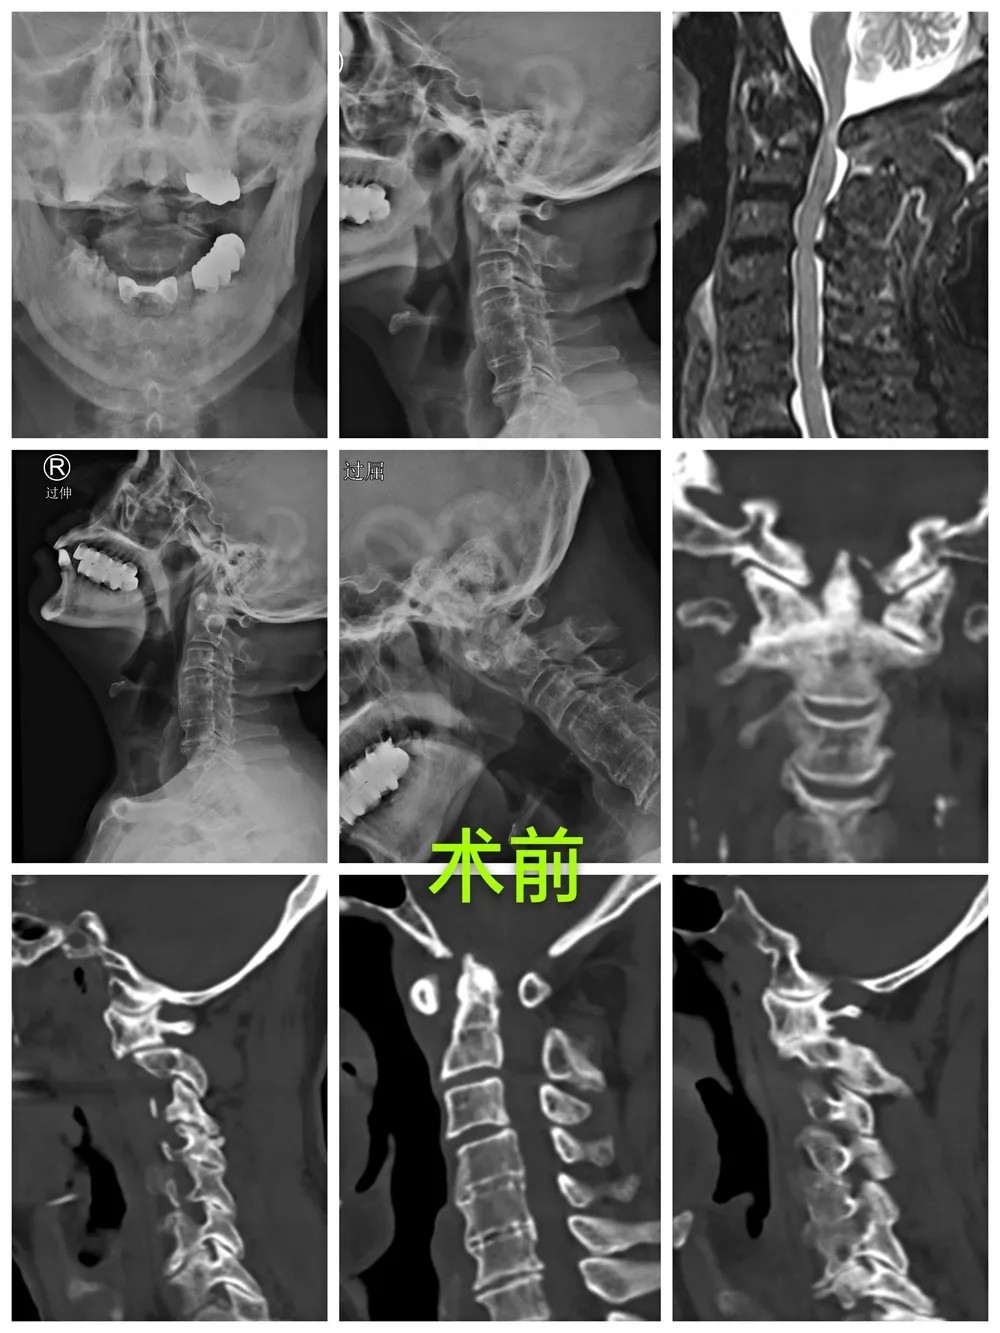

After taking a careful consideration into his medical history, physical examination and the imaging results, Prof. Lin confirmed his diagnosis that the patient had several cervical vertebra problems, including atlantoaxial dislocation, upper cervical myelopathy and high-riding left vertebral artery, so he recommended that a surgery should be performed as soon as possible. When it came to design the operative plan, there were two factors that need to be considered. One was that the patient is already 80 years old, and the other was that he had high-riding left vertebral artery with the vertebral artery dominance, which may result in a higher risk of vascular injury if a screw is used, and may further cause serious complications such as cerebral infarction or even death after surgery. After considerable discussion, the team of Prof. Lin decided to perform the surgery by following three steps: firstly, performing gradually great weight skull traction for positioning the dislocated cervical vertebra under general anesthesia; secondly, precisely inserting the screws with the help of “Tianji” surgical robot; thirdly, decompressing under 3D microscope that enables a high-definition visualization of the process.